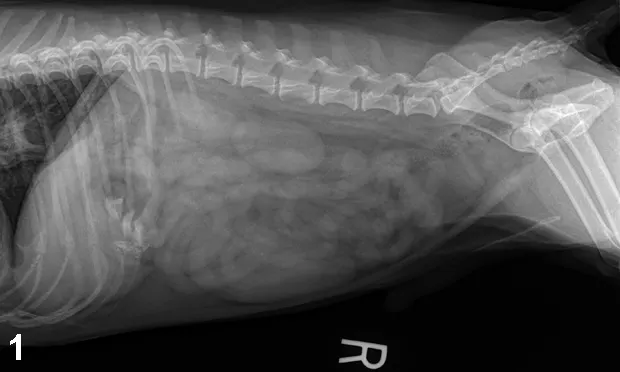

• Thoracic/abdominal radiographs: caudal esophageal foreign body (bone opacity); small nonobstructive pieces of bone in stomach, gas-filled stomach, no evidence of aspiration pneumonia or pneumomediastinum, no evidence of gastric or small intestinal obstruction (Figures 1–5).

Figure 1. Right lateral abdominal view